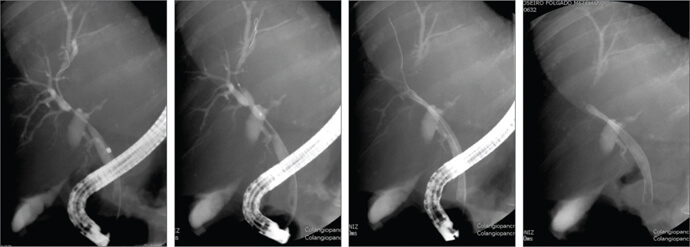

Case 2

A 63-year-old patient was admitted with obstructive jaundice. CT and MRI showed pancreatic head mass with hepatic metastasis. In cholangiogram we observed 2 stenoses in CBD (hilar and distal segment). We used the 80 mm Evolution Biliary uncovered stent with resolution of both stenoses.